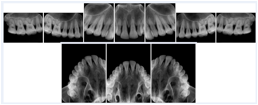

3. A dental provider wishes to capture a series of DICOM IO images for the patient’s dentition. The tooth morphology, teeth are divided into molars, premolars, canines and incisors, and a number of images for each jaw. The anatomic information was captured utilizing the triplet of schema. This standard code sequence is based on ISO 3950-2010, Dentistry - Designation system for teeth and areas of the oral cavity.

Every IO image should have anatomic information either through the primary or modifier sequence.

In most standard cases, images are oriented in structured layouts. These structured displays are useful to be shared between providers for reference purposes.

Table OO.1.1-1 shows structured display standard templates, where Viewset ID is based on the Japanese Society for Oral and Maxillofacial Radiology (JSOMR) classification provided by JIRA (Japan Medical Imaging and Radiological Systems Industries Association, www.jira-net.or.jp). Expected or typical teeth to be imaged location, region and designation codes are based on ISO 3950-2010, Dentistry - Designation system for teeth and areas of the oral cavity. For all the hanging protocols listed in OO.1.1-1, the value to use for Hanging Protocol Creator (0072,0008) is "JSOMR" and the value to use for Hanging Protocol Name (0072,0002) does not include "JSOMR" (e.g., "DL-S001A", not "JSOMR DL-S001A").

Table OO.1.1-1. Hanging Protocol Names for Dental Image Layout based on JSOMR classification